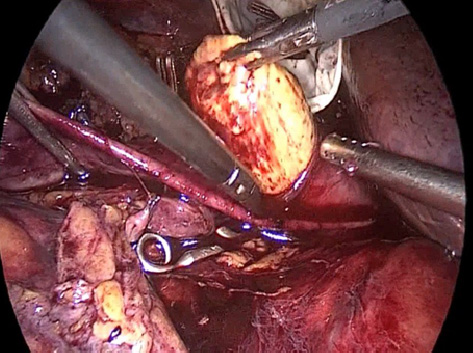

С целью проведения аортокавальной и паракавальной лимфодиссекции была проведена визуализация общей подвздошной вены с последующим переходом НПВ. На этом этапе выполнялась мобилизация как НПВ, так и контралатеральной почечной вены. Затем выделяли почечную артерию, трижды клипировав её клипсами Hem-o-lock. После пересечения клипированной почечной артерии выделяли почечную вену, в просвете которой определялся опухолевый тромб. На дистальный и проксимальный край мобилизованной нижней полой вены и контралатеральную почечную вену накладывался турникет либо сосудистый зажим «бульдог». После выполнения рассечения передней стенки НПВ, экстракции тромба из её просвета и ушивания стенки нижней полой вены выполнялся этап лимфодиссекции. На рис. 3–9 показаны данные при опухолевых тромбах 1–2-го уровней.

Рис. 4. Этап наложения сосудистых турникетов на нижнюю полую вену ниже и выше краниальной границы опухолевого тромба, рассечение стенки почечной вены у места впадения в нижнюю полую вену

Рис. 5. Этап рассечения стенки левой почечной вены с «вывихиванием» опухолевого тромба из просвета сосуда. Верхушка опухолевого тромба (желтое)